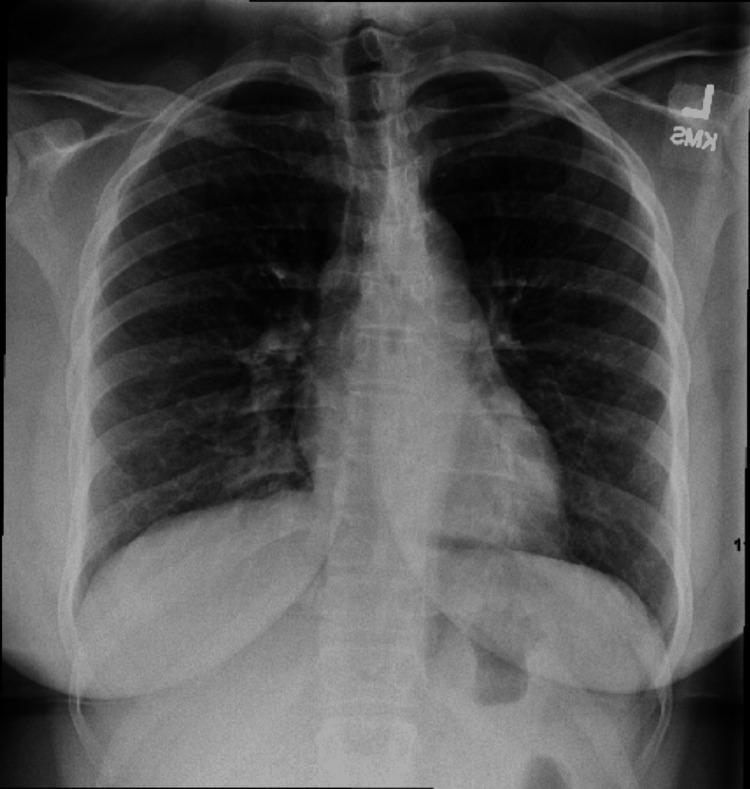

Community-acquired pneumonia is a leading cause of death from infectious diseases globally. Parapneumonic effusion is one of the most common complications of community-acquired pneumonia. As the infection progresses within the pleural space, loculation and empyema may develop. In rare cases, the parapneumonic effusions can progress significantly within 24 hours, which has been described as explosive pleuritis and may confer additional morbidity. Group A is the leading causative microorganism, which in itself has higher rates of parapneumonic effusions. We describe the case of a 30-year-old-female with a past medical history of asthma who presented to the emergency department with a sore throat, cough, and runny nose and was discharged on the same day after treatment of asthma exacerbation with upper respiratory tract infection. She re-presented within 24 hours with shortness of breath and right-sided pleuritic chest pain. Chest x-ray showed a new, large right-sided pleural effusion for which pleural fluid culture grew group A . She ultimately had prolonged hospitalization, requiring chest tube placement, and video-assisted thoracoscopic surgery (VATS). VATS was unsuccessful and she was treated with long-term antibiotics. This case demonstrates the dramatic evolution of explosive pleuritis and highlights the typical challenges encountered in these cases.

社区获得性肺炎是全球感染性疾病导致死亡的主要原因之一。类肺炎性胸腔积液是社区获得性肺炎最常见的并发症之一。随着感染在胸腔内进展,可出现分隔和脓胸。在罕见情况下,类肺炎性胸腔积液可在24小时内显著进展,这被描述为暴发性胸膜炎,可能会带来额外的发病率。A组是主要的致病微生物,其本身导致类肺炎性胸腔积液的发生率较高。我们描述了一名30岁女性的病例,她有哮喘病史,因咽痛、咳嗽和流涕到急诊科就诊,在治疗哮喘急性加重合并上呼吸道感染后于当天出院。她在24小时内再次就诊,出现气短和右侧胸膜炎性胸痛。胸部X线显示右侧有新的大量胸腔积液,胸腔积液培养生长出A组 。她最终住院时间延长,需要放置胸管,并接受了电视辅助胸腔镜手术(VATS)。VATS手术未成功,她接受了长期抗生素治疗。该病例展示了暴发性胸膜炎的急剧演变,并突出了这些病例中遇到的典型挑战。